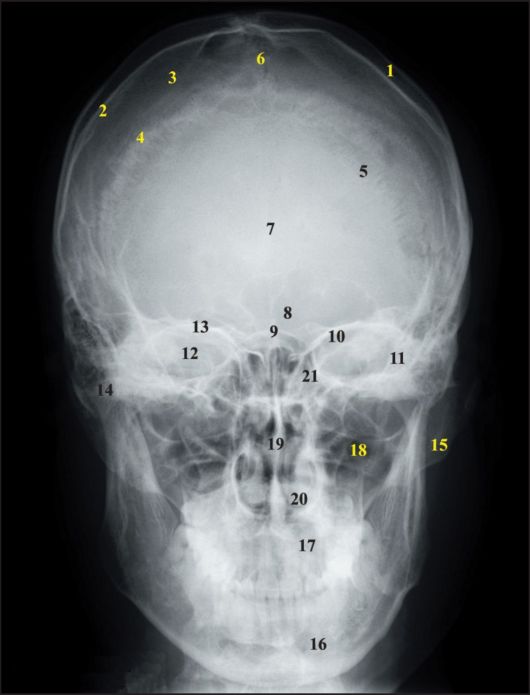

Анатомия детского черепа: Рентгеновские снимки и описание